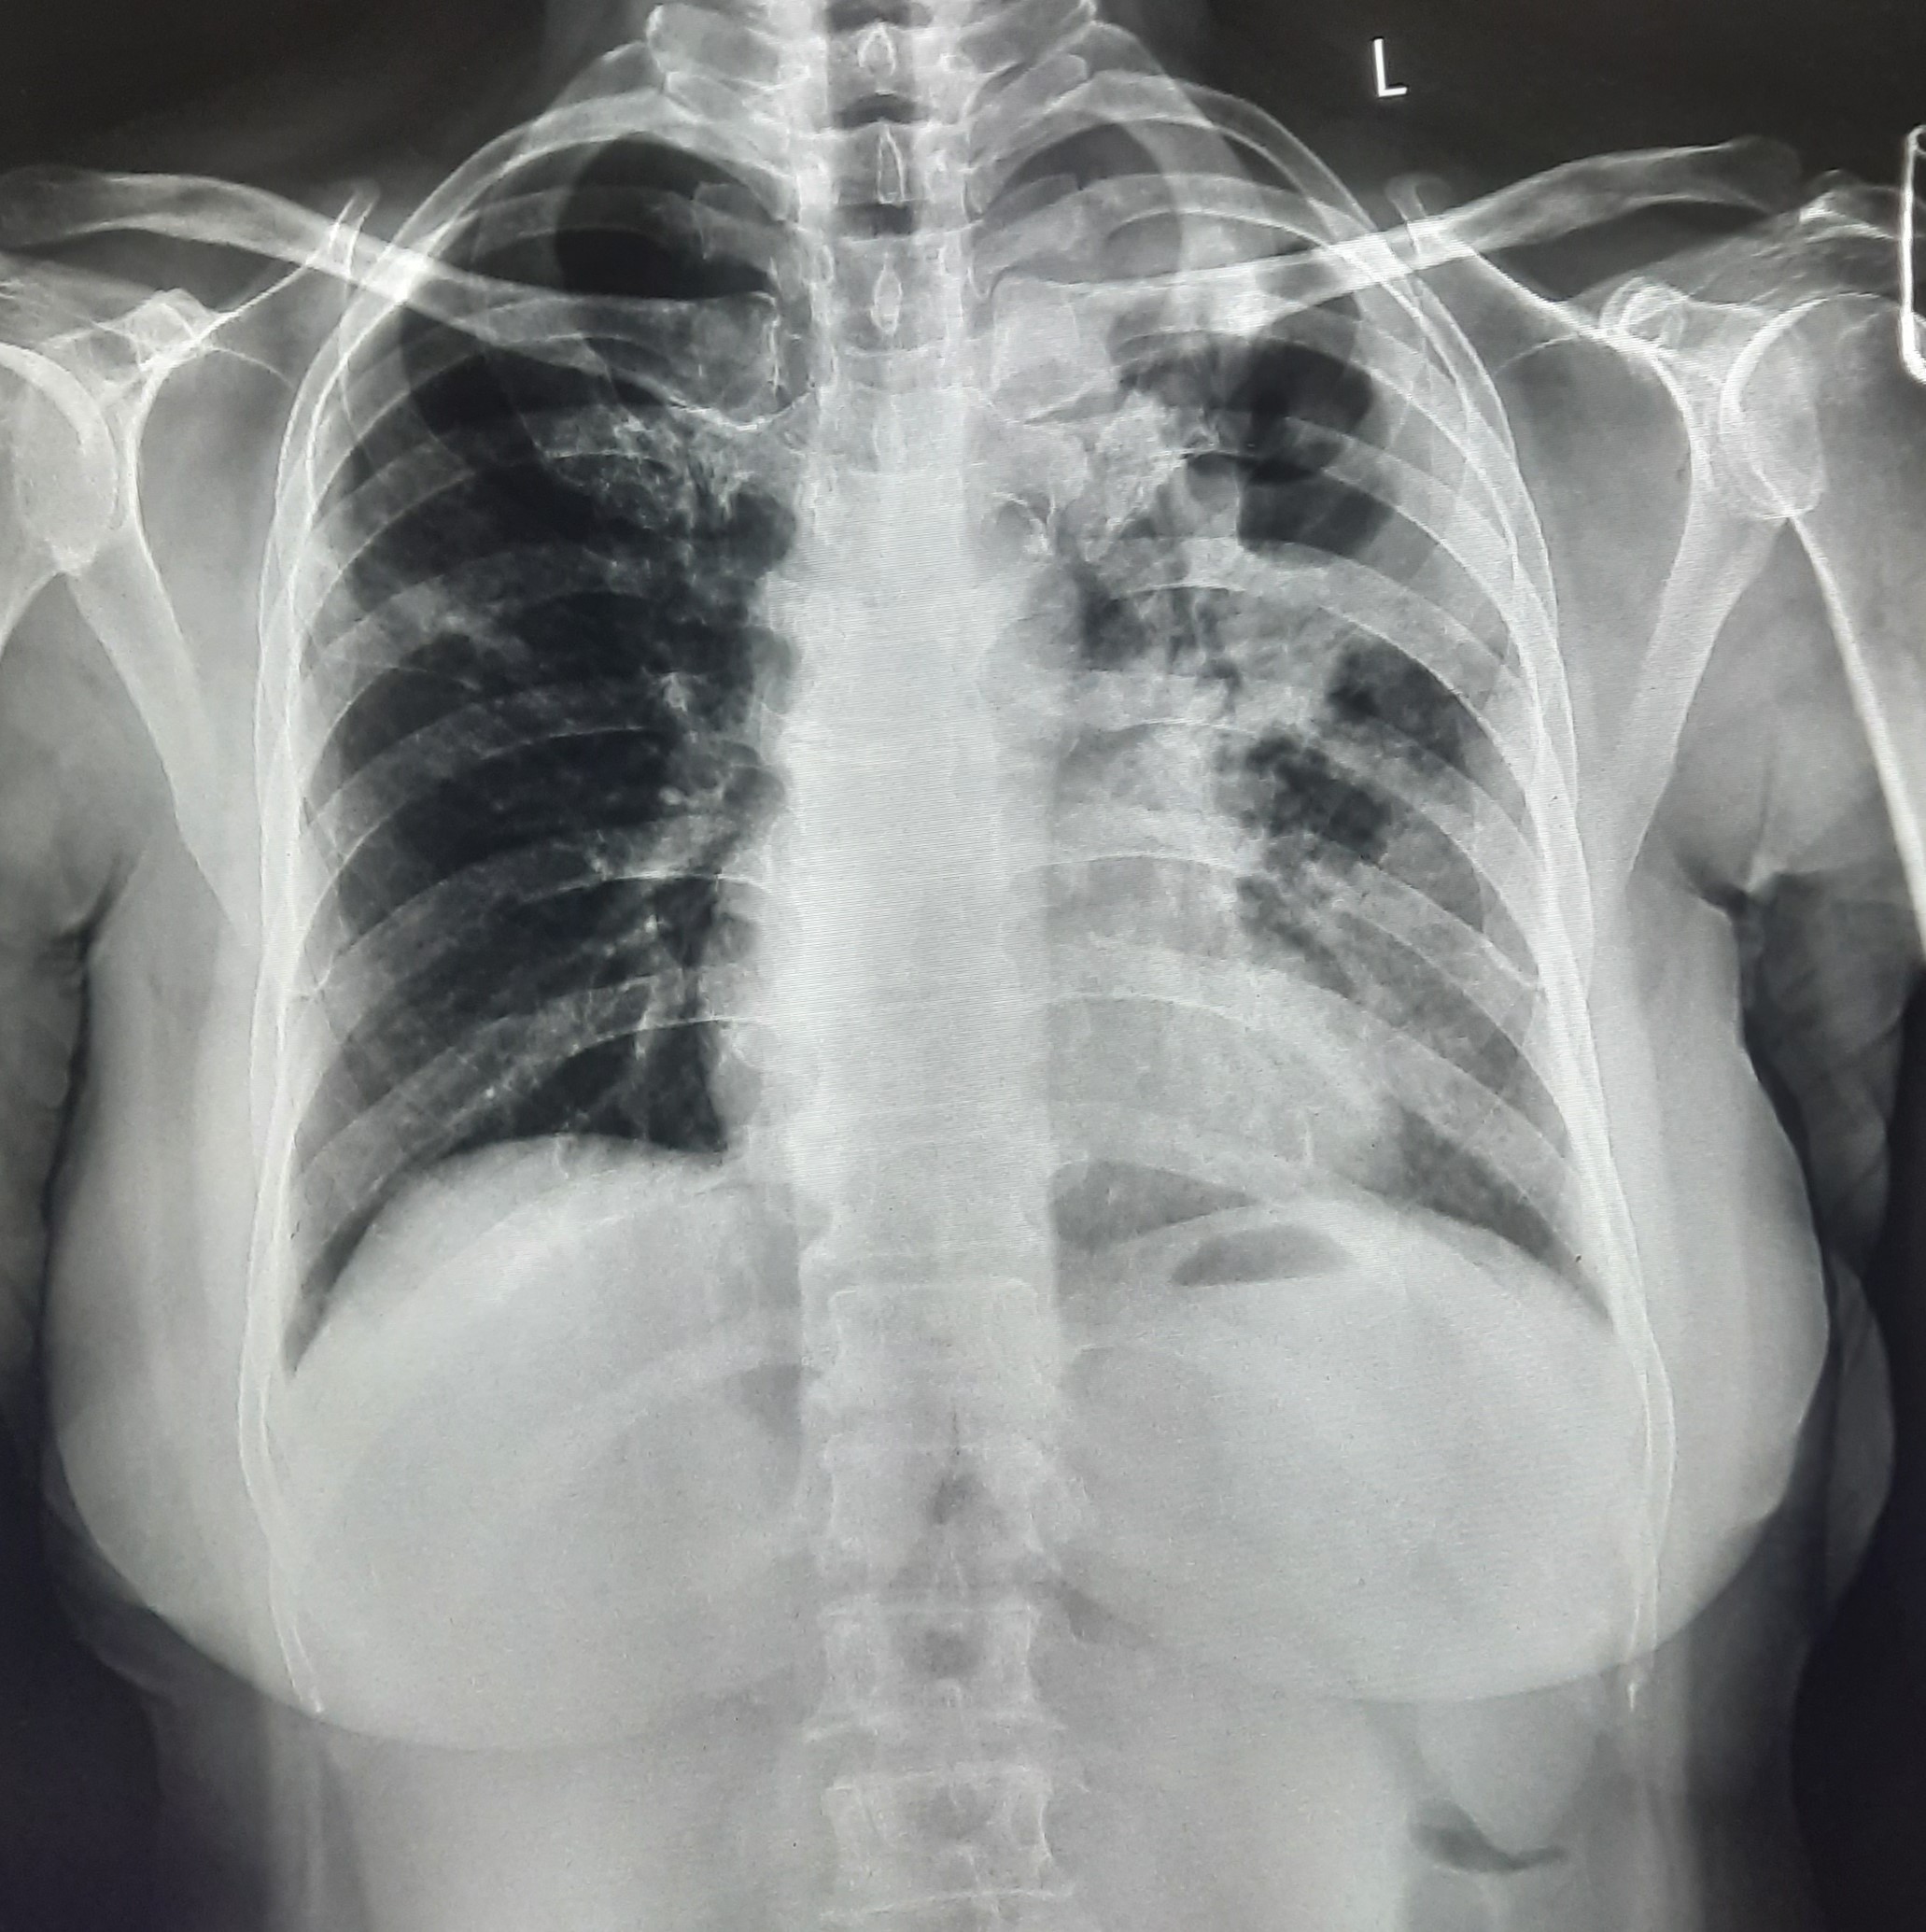

| 61 | IGGMC, Nagpur, Nagpur | P2 | 29-4411 | Roshan Ghushor | Consent taken on Paper | 32 Yrs. |

Provisional Diag : Post TB Sequelae With PTB Reactivation?

Final Diag : Pulmonary Tuberculosis |

TB Case (Confirmed) | Right Upper Zone Fibro cavitary Lesion Present, Right Mid Zone, Left Upper Zone, Mid Zone & Lower Zone Infiltration Present | Abnormality visible on x-ray |